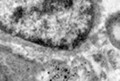

2. Transmission Electron Microscopy Processing unit

Electron Microscopy (EM): Basically two types:

1. Transmission Electron Microscope2. Scanning Electron Microscope

1. Transmission Electron Microscope (TEM) processing unit2. Scanning Electron Microscope (SEM) processing unit3. Ultra Microtome and Histopathology4. Experience in the field of specimen preparation for past 16 years